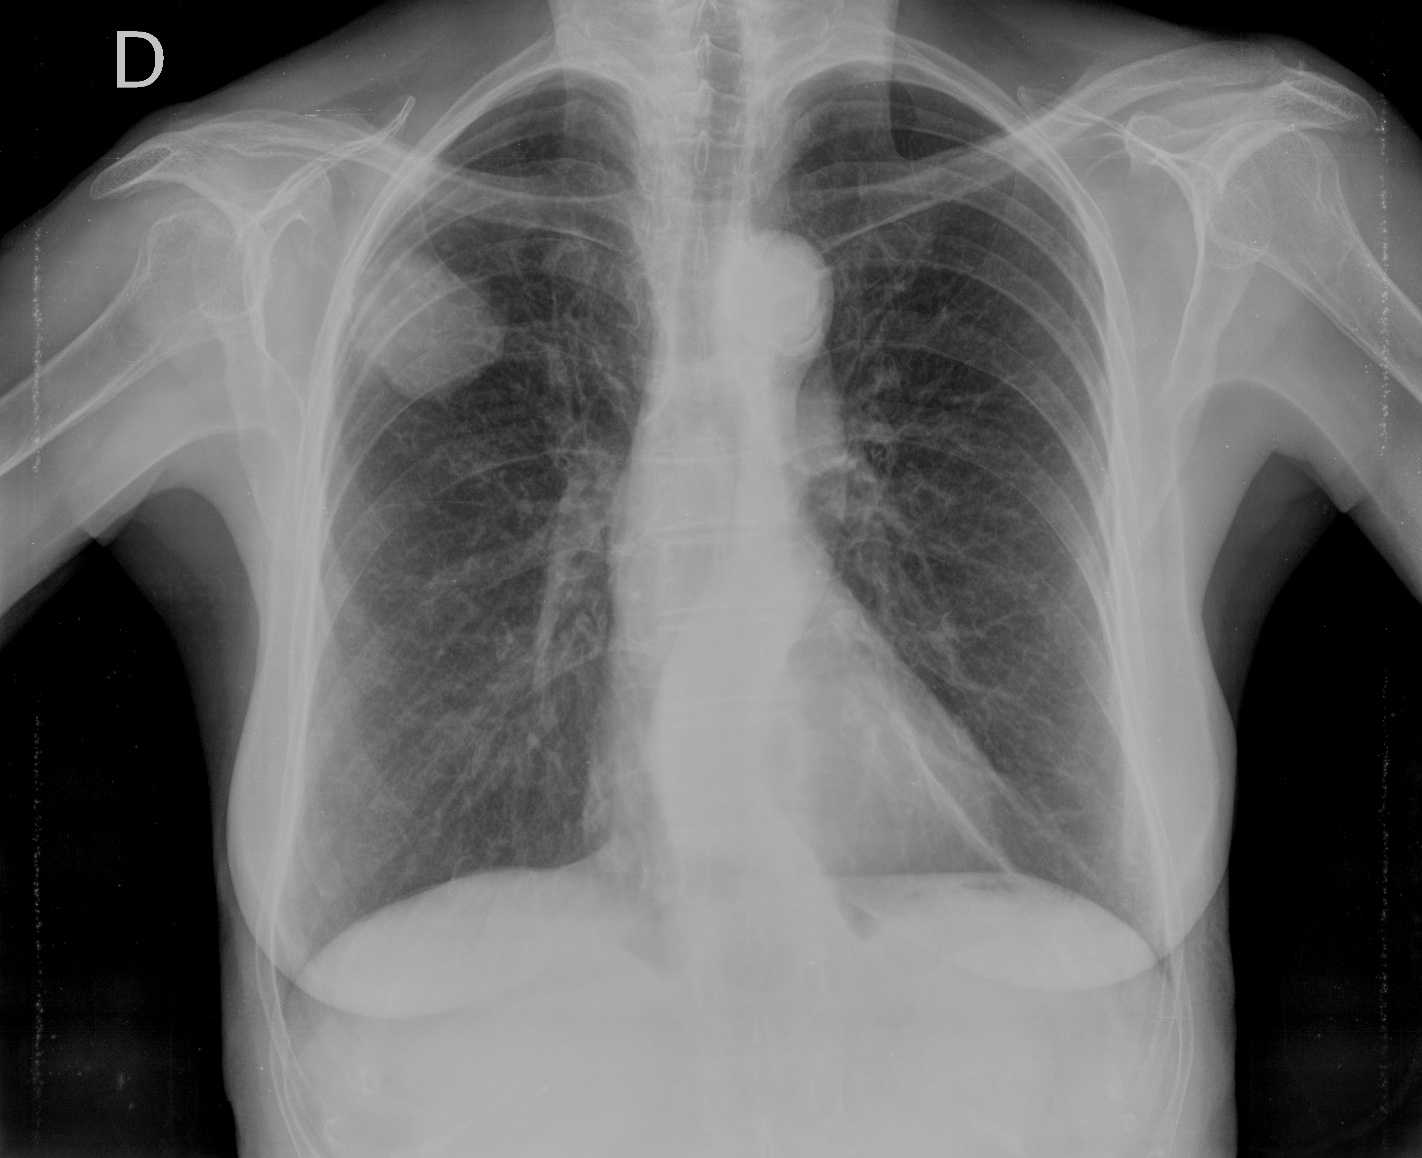

Solución: Es un estudio Normal. Silueta cardiomediastínica y parénquimas pulmonares sin alteraciones significativas.

- Comprobar que la placa está bien centrada e inspirada (6 arcos costales anteriores ó 9 posteriores).

Nota: ¡¡¡No olvidar la placa lateral!!! La regla a seguir es la misma. Leer abdomen y diafragma, examinar parte posterior, tejidos blandos y subir por la columna; tráquea y descender por mediastino. Finalmente pulmones.